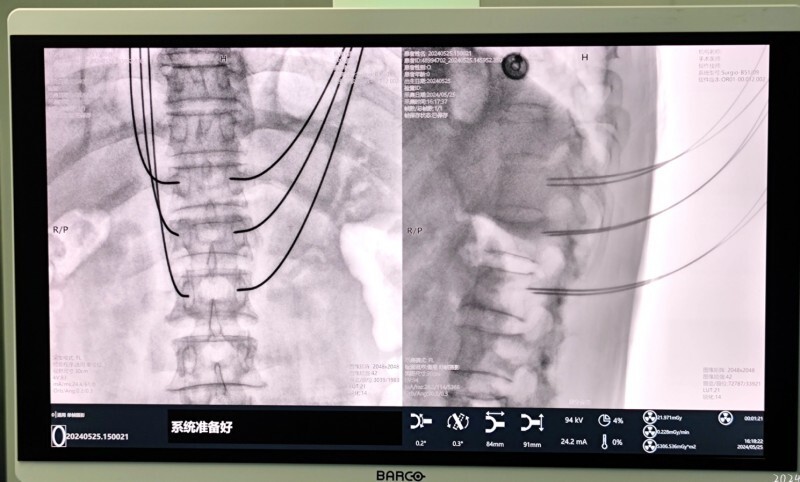

在手术室,首先对患者骨折部位进行3D影像采集,影像通过5G网络实时传输到杭州邦尔骨科医院远程会诊中心,根据扫描影像规划通道螺钉位置,通过机器人导航精确成功完成了T12椎体复位钉棒内固定手术。

“天玑”的“一臂之力”使手术定位精度达到亚毫米级,可减少术中辐射70%以上,大大提升手术效率,减少患者的射线暴露,天玑骨科机器人的“眼”、“脑”、“手”配合让高难度骨科手术实现“看得见”“打得准”“拿得稳”。